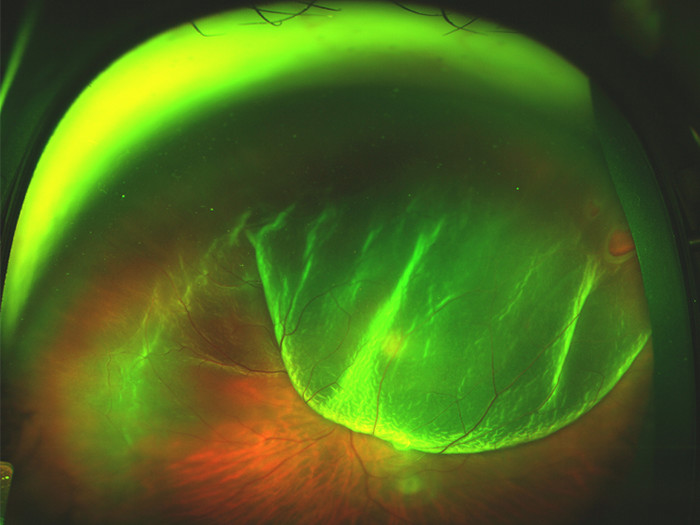

増殖性糖尿病性網膜症として知られる糖尿病性網膜症の最も進行した段階では、酸素が枯渇した網膜内に異常な血管が発生します。これらの血管は、硝子体液に漏出して瘢痕組織を形成することで視覚に影響を及ぼし、網膜を移動させたり裂いたりする可能性があります。